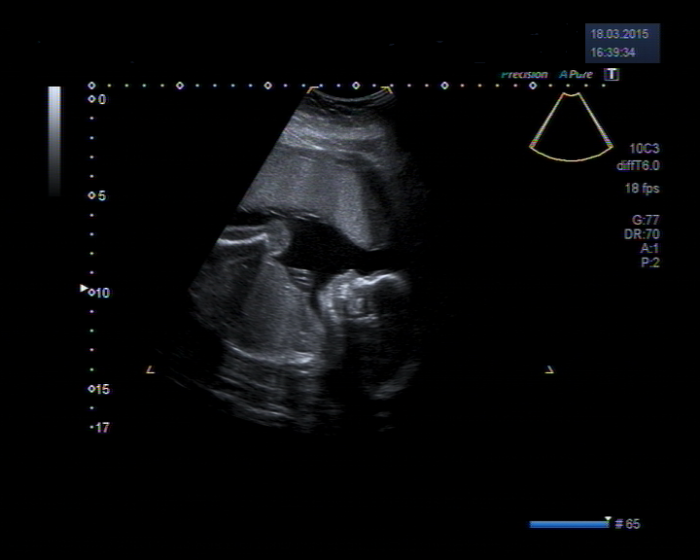

Ahoj holky těhulky, tak i my máme za sebou velký UTZ a všecko v pořádku. Akorát ta holka se nekoná

. Je to chlapec, takže se musim trochu přeorientovat.... bylo to překvápko. Když paní doktorka řekla tady je penis tak jsem působila jako idiot, páč v tom zmatení jsem se jí zeptala: "A kde maj jako holky penis??" pak se na mě jen soucitně podívala a počkala až mi to dojde. A já si byla TAK jistá tou holkou

. Přítel je nadšen, já zaskočena. UTZ trval hodinu a pár minut a všecko nám dr. ukázala, bomba. Akorát mám nějak moc plodové vody, což něvím co znamená a nechci to ani zjišťovat, abych se nevyděsila. Jdu na nějakou spešl kontrolu, tak uvidíme. Prcek má 26cm a 384g

. Přítel měl porodní váhu 4995g a 54cm a šel přirozeně....tak začínám mít trochu obavy